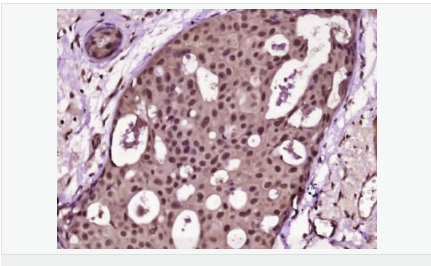

| 產(chǎn)品應(yīng)用 | ELISA=1:5000-10000 IHC-P=1:100-500 IHC-F=1:100-500 Flow-Cyt=1μg/Test (石蠟切片需做抗原修復(fù)) not yet tested in other applications. optimal dilutions/concentrations should be determined by the end user. |

| 產(chǎn)品介紹 | Proliferation Marker Ki67 antigen is the prototypic cell cycle related nuclear protein, expressed by proliferating cells in all phases of the active cell cycle (G1, S, G2 and M phase). It is absent in resting (G0) cells. Ki67 antibodies are useful in establishing the cell growing fraction in neoplasms (immunohistochemically quantified by determining the number of Ki67 positive cells among the total number of resting cells = Ki67 index). In neoplastic tissues the prognostic value is comparable to the tritiated thymidine labelling index. The correlation between low Ki67 index and histologically low grade tumours is strong. Ki67 is routinely used as a neuronal marker of cell cycling and proliferation. Function: Thought to be required for maintaining cell proliferation. Subcellular Location: Nucleus. Chromosome. Predominantly localized in the G1 phase in the perinucleolar region, in the later phases it is also detected throughout the nuclear interior, being predominantly localized in the nuclear matrix. In mitosis, it is present on all chromosomes. Similarity: Contains 1 FHA domain. SWISS: P46013 Gene ID: 4288 Database links: Entrez Gene: 4288 Human Entrez Gene: 17345 Mouse Omim: 176741 Human SwissProt: P46013 Human SwissProt: Q91VE6 Mouse Unigene: 689823 Human Unigene: 80976 Human Unigene: 4078 Mouse Unigene: 233802 Rat Important Note: This product as supplied is intended for research use only, not for use in human, therapeutic or diagnostic applications. 細(xì)胞增殖標(biāo)志物(Proliferation Marker) Ki67與PCNA一樣,為細(xì)胞增殖的一種標(biāo)記,在細(xì)胞凋亡中S、G2 、M期均有表達(dá),G0期缺如。 Ki-67增殖指數(shù)高低與許多腫瘤的分化程度、浸潤、轉(zhuǎn)移以及預(yù)后密切相關(guān),因此被廣泛作為各種惡性腫瘤的必檢項(xiàng)目之一。 |